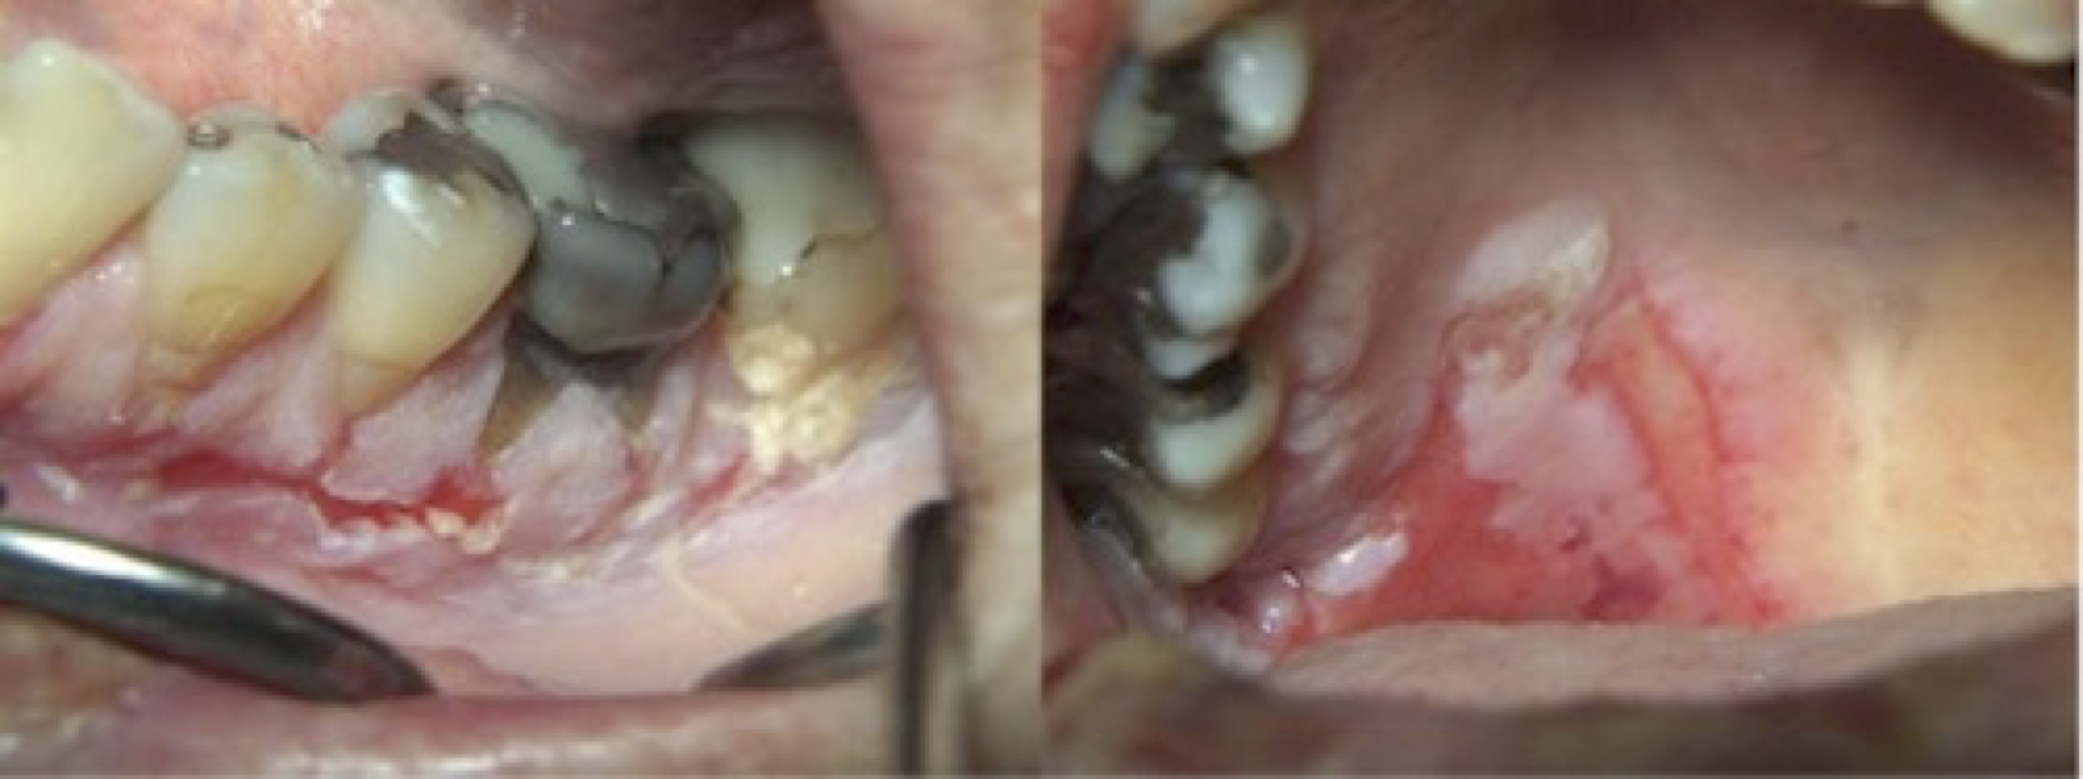

KLINISKT UTSEENDE

De intraorala lesionerna kan variera i utseende och utbredning. Initialt kan man i enstaka fall se de ytliga blåsbildningarna men oftast manifesterar sig PV som sårbildningar där det intilliggande epitelet släpper vid lätt mekanisk belastning (Nikolskys tecken). Såren är ofta tämligen skarpt avgränsade från den intilliggande vävnaden. Inte sällan har munslemhinnan där epitelet fortfarande sitter kvar en lätt vitaktig ton på grund av akantolysen (Bild 1, 2) som också i någon mån därmed maskerar den inflammatoriska processen. Lesionerna kan sitta var som helst i munhålan, men engagemang av gingiva och gomslemhinna är vanligt.